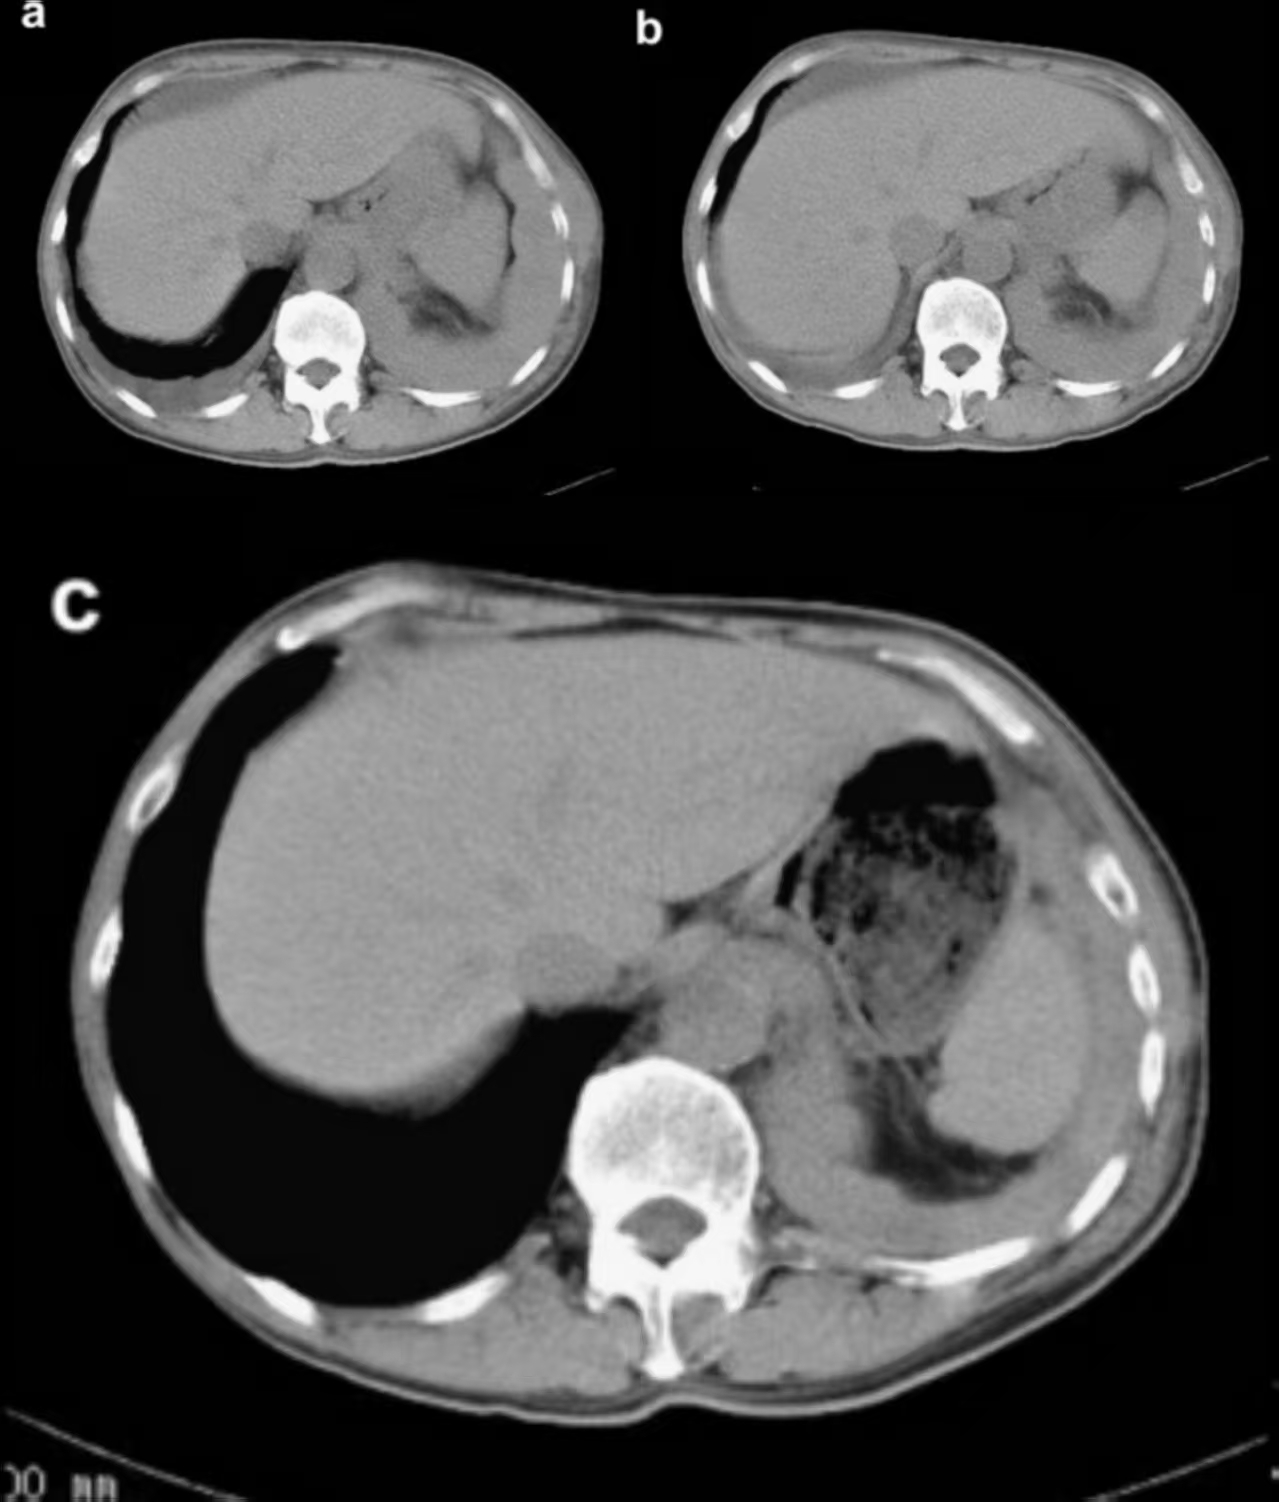

一位78岁女性上唇肿块形成3个月,经过检查发现,在左上中切牙至尖牙区域的唇颊沟处有一形态不规则的肿瘤样肿物。活检后,诊断为乳头状囊腺癌。患者拒绝接受手术治疗、化疗及放疗。之后肿瘤在三年半的时间里逐渐增大,在拒绝接受手术的情况下,患者最终同意接受硼中子俘获疗法(BNCT)。